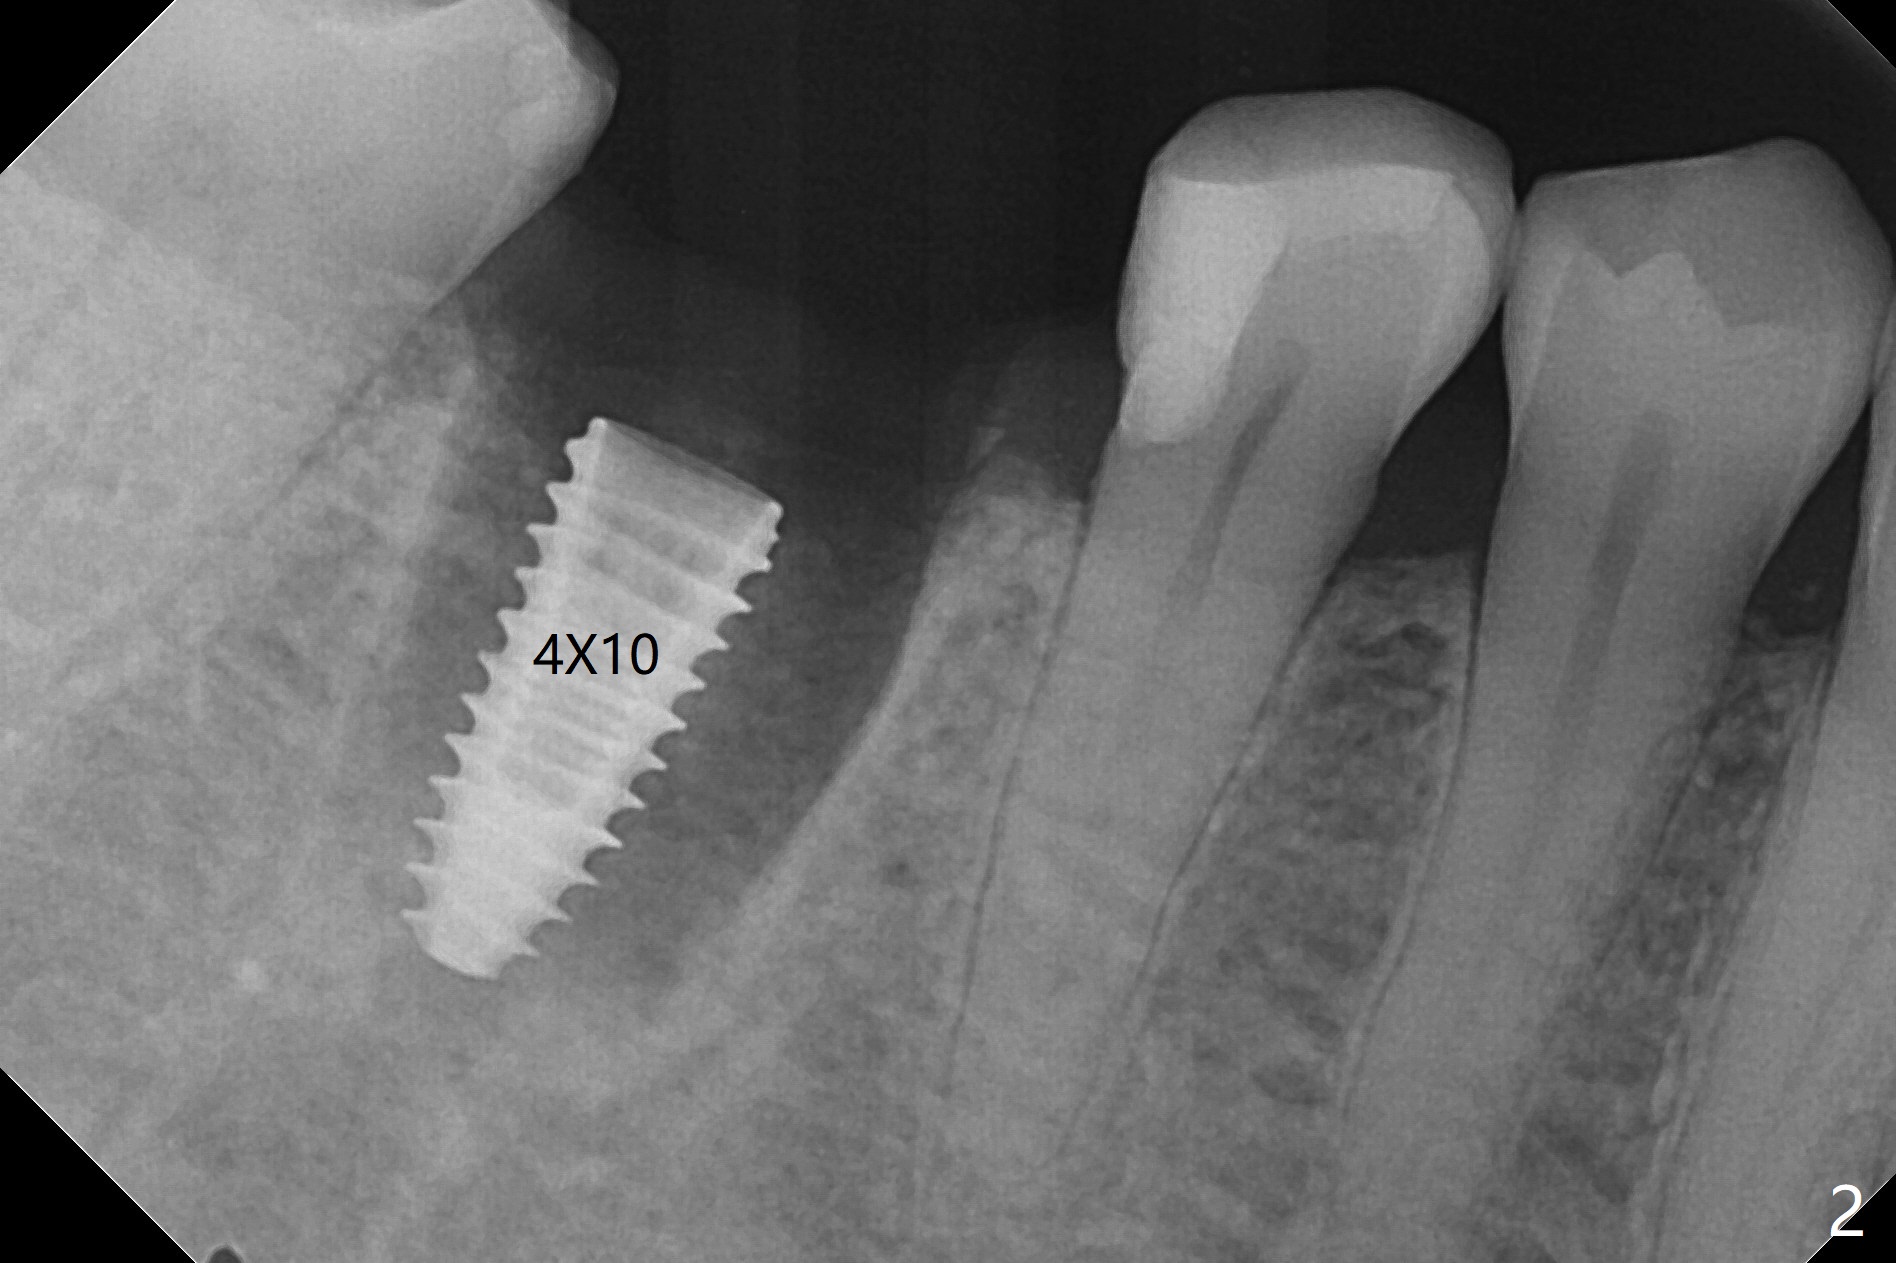

牙冠断裂,好像容易保留牙根,其实还挺多工作。使用12毫米平磨钻头后,中隔中央形成凹陷,不过使用2.2x7.3毫米钻头后,钻洞开始偏移远中(图一)。完成3.5x11.5毫米钻洞,4x10毫米报废植体扭力很高(图二)。为了植入5x11毫米植体(扭力35Ncm),必须使用4.5x11.5毫米钻头(图三)。虽然根尖骨质不多,稳定性部分来自残余颊侧,舌侧中隔。即刻放置的基台远中舌侧必须大量磨去(图四:^)才有足够空间做临时牙冠,说明牙冠会折裂病人咬合力大。保留牙根工作量大,仍有偏差(与图五(设计)相比),仿佛好处不大,以后少做。由于临时牙冠舌侧做的大些,术后八天取出修正,伤口愈合正常(图六)。术后一个月一部分骨粉好像被转化为牙龈(图七)。术后3.5月病人抱怨咀嚼疼痛,植体松动,放置愈合基台。一个月后植体仍松动,疼痛(图八)。术后6.5月,植体不再松动,放置修复基台(图九),取模。